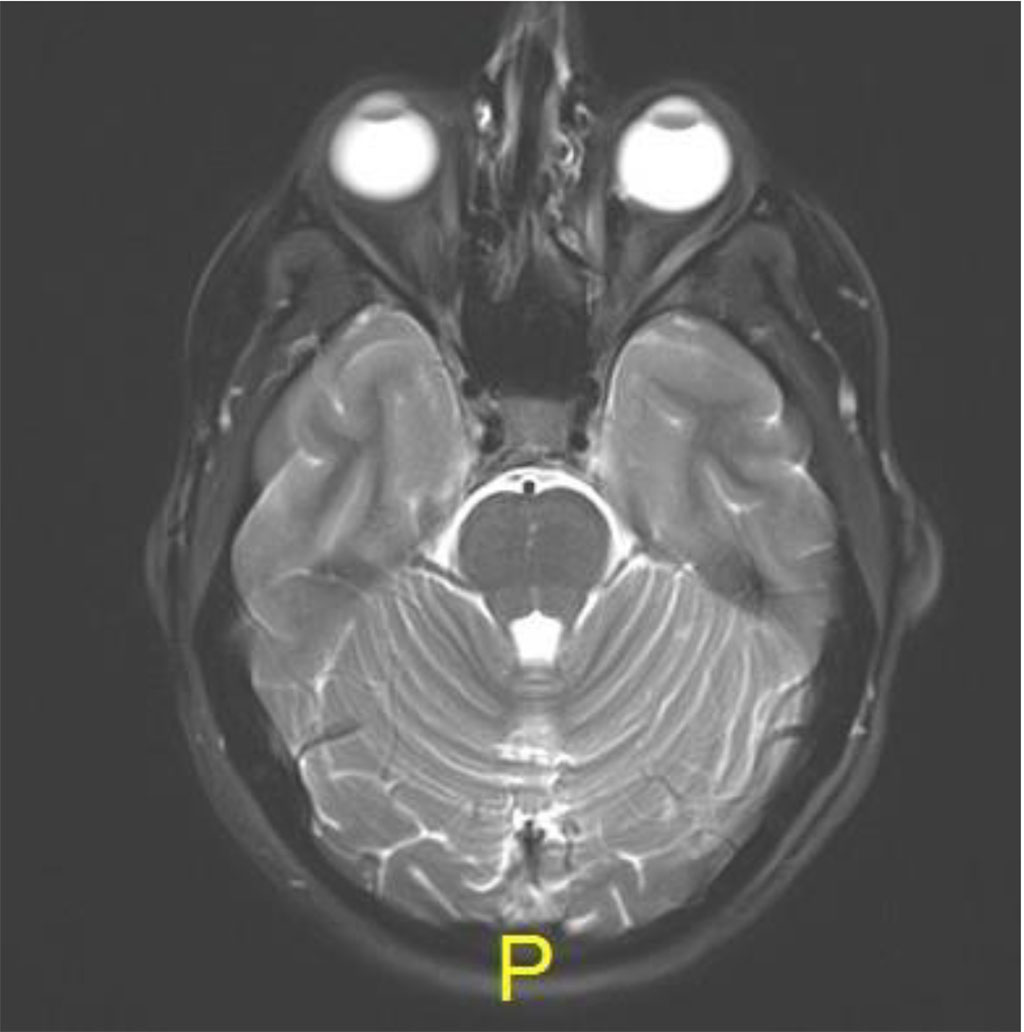

Following the procedure, the patient complained of diplopia in primary position with restriction of upgaze. The patient was treated with oral steroids with no improvement. MRI was 2 months post procedure, there was excellent anatomical improvement, with significant decrease of the lesion but with enlargement of the inferior rectus (Figures 4 a,b,c).

Figure 4a: Axial MR T2: resolution of lesion

Figure 4c: Coronal MR T2: Complete resolution of lesion